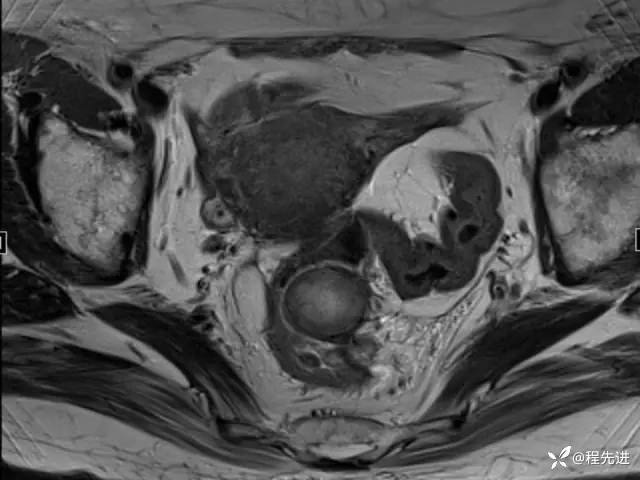

MRI平扫+增强:

T2:

T2矢状位: